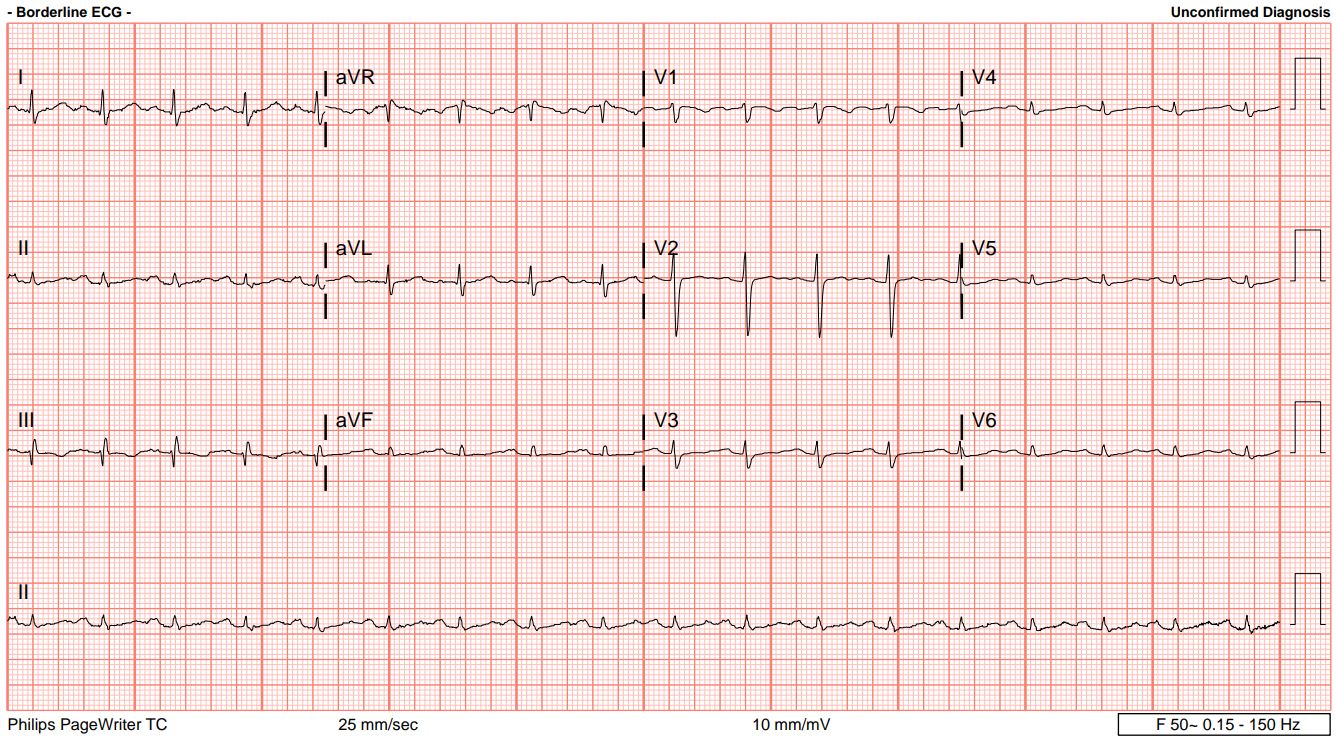

A 42-year-old woman with no known medical illness presented to the ED with shortness of breath for the past 5 days, which acutely worsened a few hours ago. On physical examination, she was tachypneic, lethargic with altered mental status, normotensive but tachycardic, and had an oxygen saturation of 92% on room air. Lung auscultation revealed reduced breath sounds bilaterally, and heart auscultation showed no murmurs. Her chest X-ray was clear, but the ECG showed a typical S1 Q3 T3 pattern.